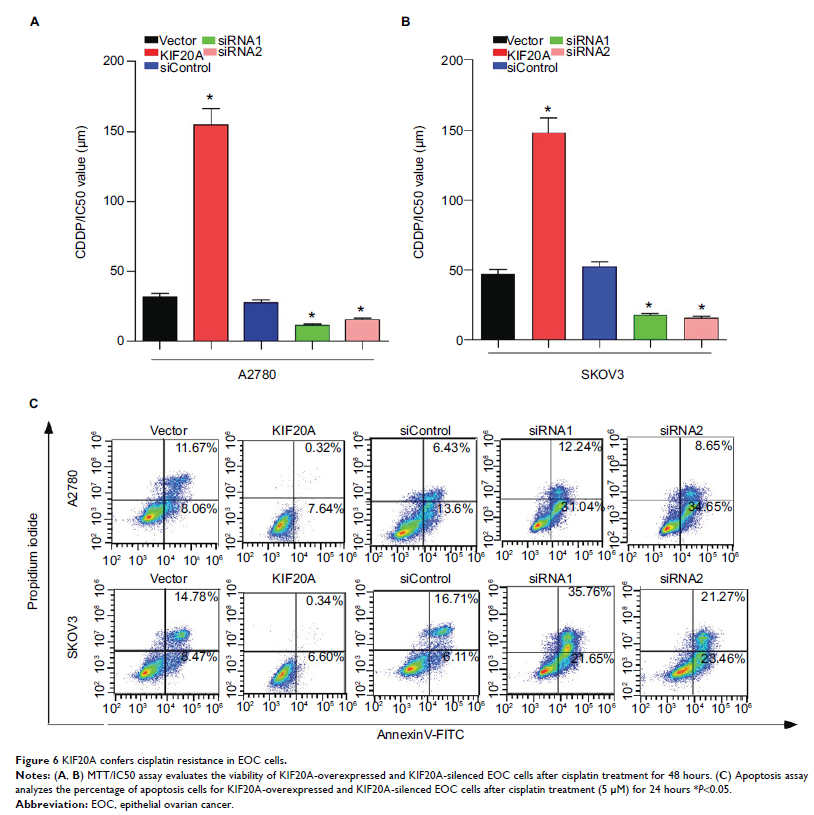

Original Research

驱动蛋白家族成员 20A 的过表达与上皮性卵巢癌的不佳临床疗效和肿瘤进展相关

- 作者:Han Li, Weijing Zhang, Xiaoying Sun, Jueming Chen, Yue Li, Chunhao Niu, Benke Xu, Yanna Zhang

- 期刊:Cancer Management and Research